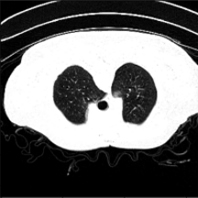

Recent studies indicate that detecting radiographic patterns on CT scans can yield high sensitivity and specificity for COVID-19 localization. In this paper, we investigate the appropriateness of deep learning models transferability, for semantic segmentation of pneumonia-infected areas in CT images. Transfer learning allows for the fast initialization/ reutilization of detection models, given that large volumes of training are not available. Our work explores the efficacy of using pre-trained U-Net architectures, on a specific CT data set, for identifying Covid-19 side-effects over images from different datasets. Experimental results indicate improvement in the segmentation accuracy of identifying COVID-19 infected regions.